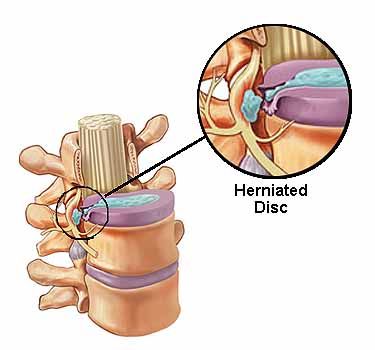

Herniated Disc

The soft discs which are present in between the vertebrates can bulge out, pressing on nearby nerves and causing pain.